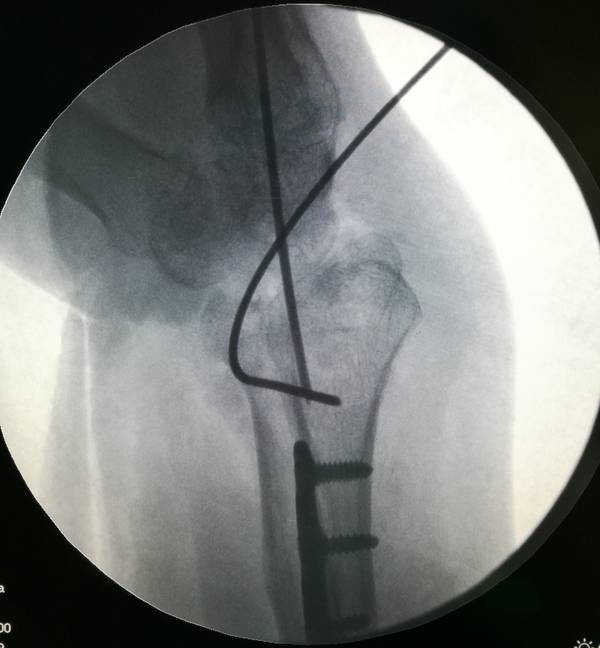

本帖最后由 zhangwenlong 于 2019-1-14 22:04 编辑

桡骨远端骨折术中透视

侧位,前臂远端抬高20度拍摄关节面切线位正位,后前位,前臂抬高13度拍摄关节面切线位

前臂树立,屈腕拍摄桡骨远端背侧切线位片

可以更好的判断螺钉长短